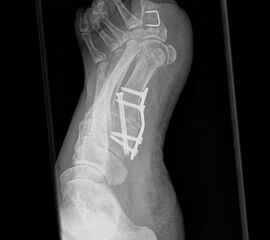

Fuß in 45° Supination ohne Belastung

Positionierung:

• Der Patient sitzt auf dem Untersuchungstisch.

• Der Fuß steht auf der Kassette, der mediale Fußrand wird um 45° angehoben (optional Verwendung eines Keilkissens).

• Der Zentralstrahl wird auf das Os naviculare ausgerichtet.

• Die Röhre ist 0° vertikal ausgerichtet.

Kennzeichen des Röntgenbildes:

• Gute Einsicht in das Tarsometatarsale I Gelenk.

Besondere Bemerkungen zum Beispielbild:

• Die 45° Supinationsaufnahme wird häufig eingesetzt, um die knöcherne Konsolidierung einer Lapidus-Arthrodese zu beurteilen.

• Hier das Beispiel 6 Wochen postoperativ nach Tarsometatarsale I Fusion mit Stabilisierung durch eine plantare Platte.

• Die Arthrodese zeigt sich weitgehend überbaut bei korrekter Lage des Osteosynthesematerials.

Zur Vollansicht und zum Lesen der Bildbeschreibung bitte die Bilder anklicken.